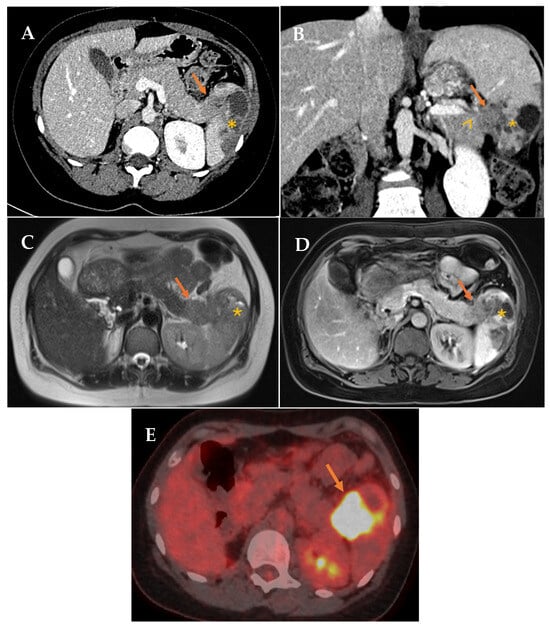

In July 2022, the patient reported left costal discomfort, prompting an Abdominal Computed Tomography (A-CT) that revealed an area of splenic infarction and a solitary mass measuring approximately 3 cm in the pancreatic tail/splenic hilum, suspicious for malignancy. Further workup with pancreatic Magnetic Resonance Imaging (MRI), 18F-fluorodeoxyglucose Positron Emission Tomography/CT (18F-FDG PET/CT) (Figure 1), and endoscopic ultrasound (EUS) with fine-needle aspiration (FNA) confirmed the diagnosis of squamous cell carcinoma, showing strong and diffuse positivity for CK 5/6 and p40.

Figure 1.

(A,B) Contrast-enhanced CT in portal phase. Axial and coronal reconstruction. Defined hypodense solid mass in the tail of the pancreas (arrow) with infiltration of the splenic hilum (arrowhead). Associated low attenuation changes in the spleen, secondary to infarction (asterisk). (C,D) Axial MRI. T2 and contrast-enhanced T1 sequences. Solid mass in the tail of the pancreas (arrow). Associated signal changes in the spleen, secondary to infarction (asterisk). (E) 18F-FDG PET/CT (18-fluorodeoxyglucose). Mass in the tail of the pancreas-splenic hilum region with pathological FDG uptake with splenic infiltration (arrow).